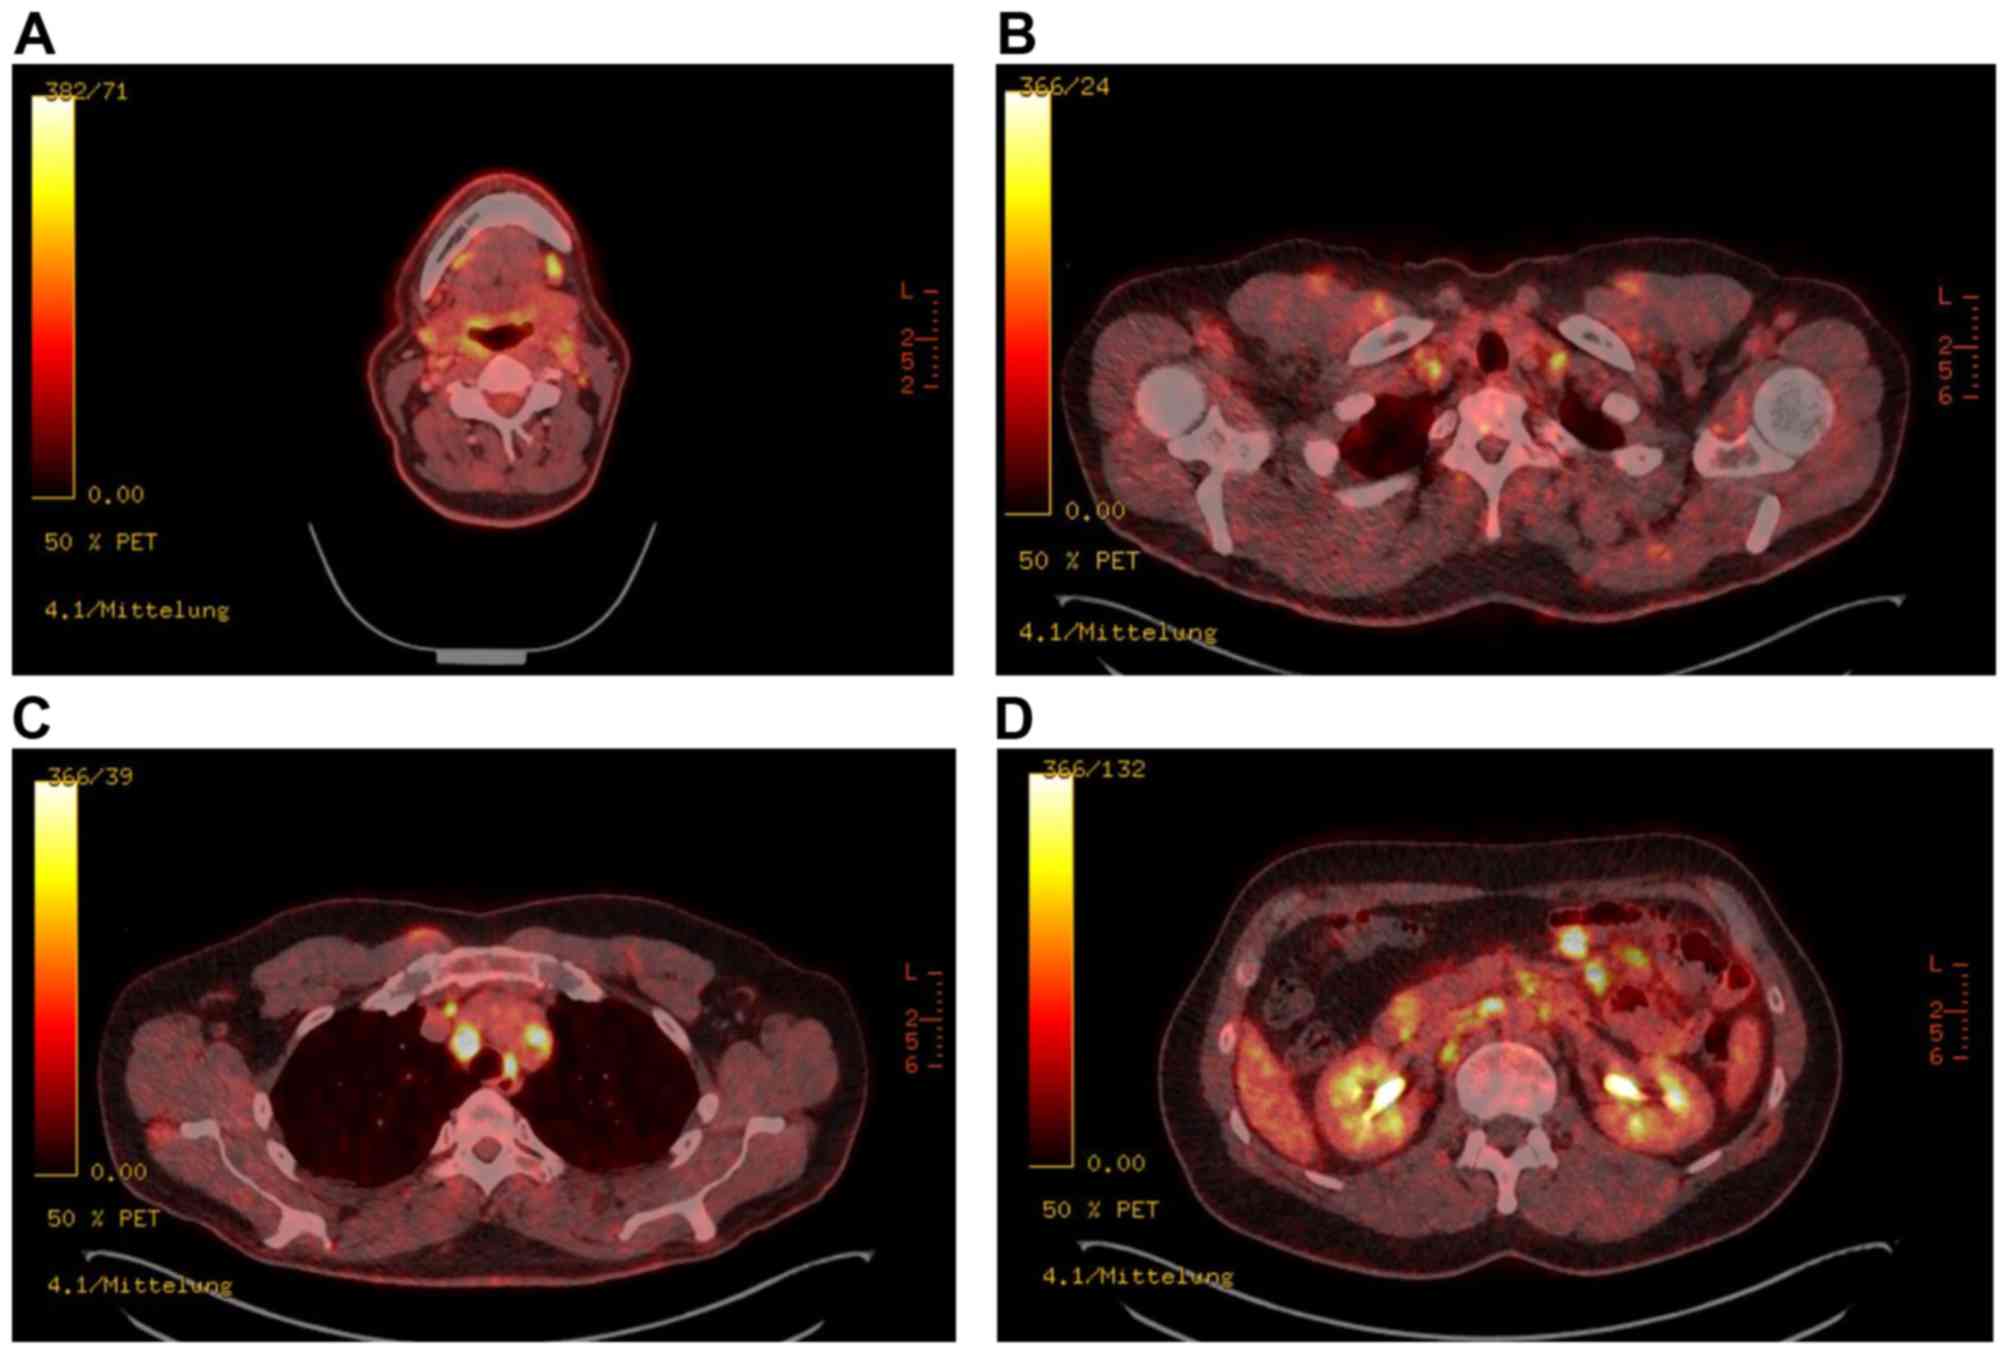

Coexistence Of Sarcoidosis And Metastatic Lesions A Diagnostic And Therapeutic Dilemma Review

Usefulness Of Pet Ct In The Diagnosis Of Recurrent Or Metastasized Differentiated Thyroid Carcinoma

www.spandidos-publications.com